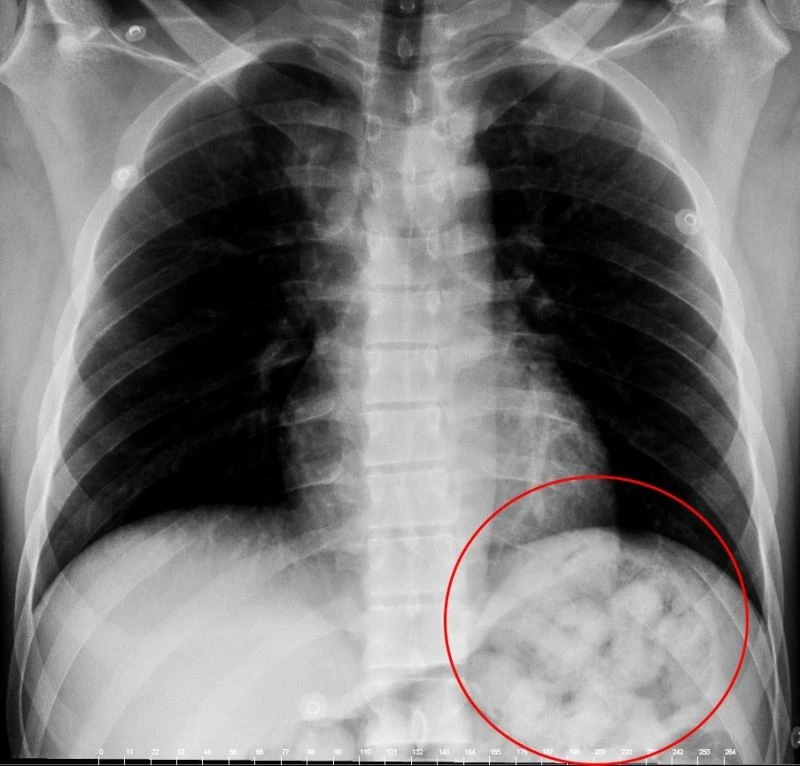

Van’dan otobüsle Ankara’ya gelen yabancı uyruklu şahıs, yuttuğu 72 kapsül metamfetamin kapsülünün midesinde patlaması üzerine rahatsızlanarak hastaneye kaldırıldı.

Edinilen bilgiye göre, 5 gün önce Van’dan otobüsle Ankara’ya gelen O. Zahed Ahmed Narziveh rahatsızlanınca hastaneye kaldırıldı. Ankara Şehir Hastanesine getirilen şahsın röntgen görüntüleri gerçeği ortaya çıkardı. Şahsın midesinde 890 gram ağırlığında 2’si patlamış halde 72 kapsül olduğu ve kapsüllerin patlaması ile fenalaştığı belirlendi. Mahkeme kararına istinaden ameliyata alınarak midesindeki metamfetamin kapsülleri çıkartılan zanlı, Ankara Emniyet Müdürlüğüne bağlı Narkotik Suçlarla Mücadele ekiplerince hastanedeki 5 günlük tedavisinin ardından adliyeye sevk edildi.